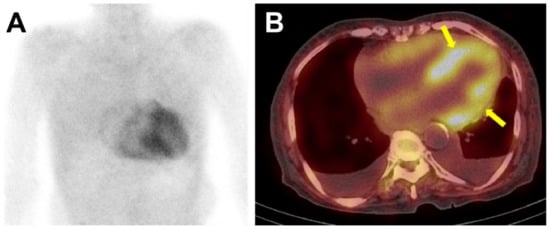

Bone scintigraphy involves the intravenous administration of 370 to 925 MBq of 99mTc-labeled bone-seeking radiotracer followed by planar and single-photon emission computed tomography (SPECT) imaging after 1–3 h. An assessment of myocardial radiotracer uptake is the mainstay in the diagnosis of ATTR-CA. The intensity of myocardial radiotracer uptake can be analyzed either by visual grading or by quantifying radiotracer uptake using the heart-to-contralateral lung ratio (H/CL ratio). The Perugini grading system is based on a visual analysis of cardiac uptake at 2–3 h delayed planar image where (1) grade 0 indicates no cardiac uptake, (2) grade 1 suggests mild cardiac uptake less than that in rib, (3) grade 2 suggests moderate cardiac uptake equal to that in rib, while (4) grade 3 indicates intense cardiac uptake greater than that in rib. Bone scintigraphy with a Perugini grade of 2 or 3 has been reported to demonstrate a high sensitivity of about 99% for ATTR-CA, but a lower specificity ranging from 82–86%, given that a grade of 1–2 can be also observed in AL-CA. However, if monoclonal gammopathy was excluded via the urine/serum test, the specificity of the test was demonstrated to be increased to almost 100% [2]. Another quantification method using the H/CL ratio is evaluated in a 1 h image after 99mTc-PYP administration [64,65]. Here, an H/CL ratio ≥ 1.5 is highly suggestive for ATTR-CA, and therefore can be used in the diagnosis of ATTR-CA. In addition to its role in diagnosis, an H/CL ratio ≥ 1.6 can be used as a worse prognostic marker [65]. An important caveat in assessment of myocardial radiotracer uptake is that a planar image alone has limitation in distinguishing between true myocardial uptake and blood pool uptake. Therefore, additional SPECT imaging is necessary to achieve more accurate localization of radiotracer uptake (Figure 4) [29].

Figure 4. The 99mTc-DPD bone scintigraphy and single-photon emission computed tomography (SPECT) of a patient with ATTR-cardiac amyloidosis. In Figure 4, the anterior planar image (panel A) showed intense, heterogeneous cardiac uptake greater than rib uptake in intensity, considered as Perugini grade 3. No abnormal radiotracer uptake was seen in other organs such as the liver or kidney. SPECT images (panel B) were acquired immediately after the planar imaging, and the radiotracer uptake could be localized to the myocardium (arrows), and not in the blood pool. Bilateral pleural effusion was also noted.